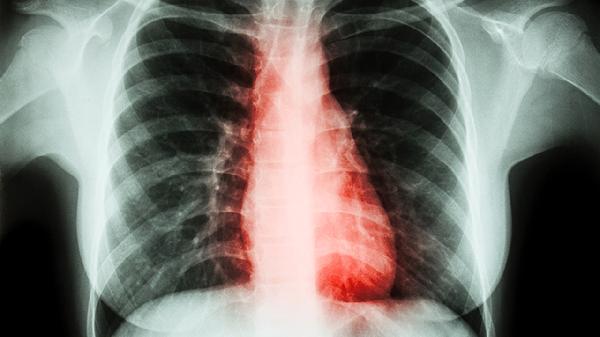

清肺散结丸对肺结节有一定治疗效果,可能与调节免疫功能、改善局部血液循环有关。肺结节患者通常伴随咳嗽、胸痛等症状,遵医嘱使用本品时可联合肺部CT复查监测病情变化。